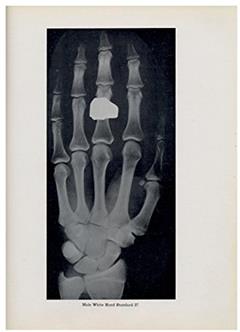

Throughout the pages (which, let's be honest, are much less thrilling than a page-turner), Todd meticulously documents different stages of skeletal development. We're talking X-rays, diagrams, and images that make every anatomy class you've ever taken seem like a beach read. He provides a comprehensive guide to understanding how bones mature from childhood into adulthood, which is basically a high-stakes game of "Will this kid be tall? Spoiler alert: It's mostly determined by genetics!"

But wait! There's more! If you manage to make it through the bone looks and medical terminology, Todd provides plenty of illustrations to guide you along. Think of them as your skeletal roadmap, navigating through the maze of human growth-only it's not as fun as a treasure hunt (unless your treasure is knowledge about bones).